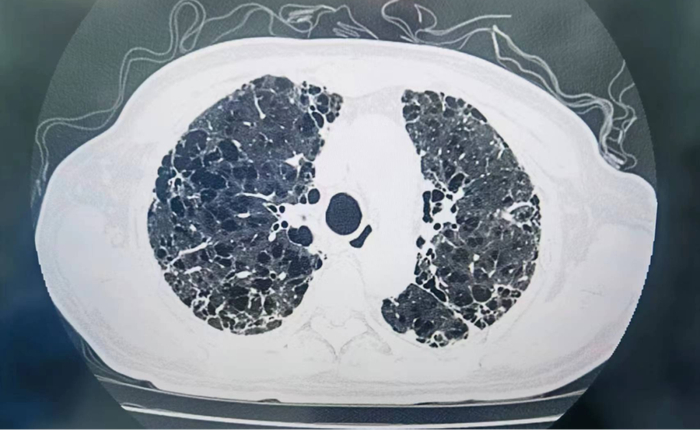

(患者术前影像检查资料)

同时接受双肺移植的另一位患者黎伯(化名)是呼吸内科的“老病号”,由于十几年的病程,已经将他的双肺摧残成马蜂窝状,大片空洞已经不可逆转,反复感染成为他的危险致命因素。